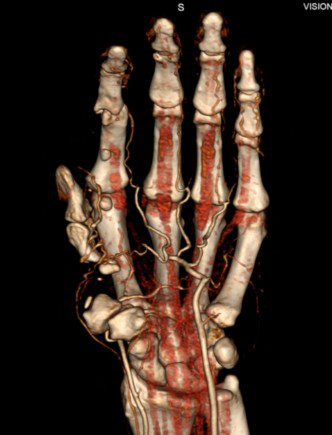

病例一 男,38歲, 拇指再植后運(yùn)動(dòng)障礙

患者拇指運(yùn)動(dòng)連續(xù)掃描采集的矢狀位重建圖像,能夠很好地顯示:再植后的拇指,主動(dòng)運(yùn)動(dòng)的掌側(cè)外展角度的變化范圍都明顯受限。

640層寬體探測(cè)器CT對(duì)于一些骨骼系統(tǒng)的疾病能夠單圈覆蓋。特殊的動(dòng)態(tài)掃描技術(shù),實(shí)現(xiàn)對(duì)于一些關(guān)節(jié)運(yùn)動(dòng)的量化分析。

在一些復(fù)雜的關(guān)節(jié)中,運(yùn)動(dòng)過(guò)于復(fù)雜,可能包含了多個(gè)運(yùn)動(dòng)結(jié)構(gòu)以及旋轉(zhuǎn)運(yùn)動(dòng), 甚至在關(guān)節(jié)振幅的極端處進(jìn)行靜態(tài)評(píng)估時(shí),不足以證明病變時(shí),動(dòng)態(tài)CT都能夠在制定運(yùn)動(dòng)過(guò)程中記錄骨骼關(guān)系的短暫變化, 這對(duì)評(píng)估復(fù)雜運(yùn)動(dòng)特別有用。